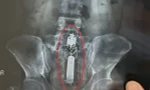

Ngày 26/3, đại diện Bệnh viện Đa khoa tỉnh Cà Mau cho biết, đơn vị vừa tiếp nhận và thực hiện các biện pháp chuyên môn lấy một dương vật giả ra khỏi trực tràng của một nam bệnh nhân 23 tuổi, ở huyện Thới Bình.

Sau khi thăm khám, bệnh viện đã chỉ định gây tê tủy sống và thực hiện thủ thuật lấy thành công một dương vật giả, có chiều dài hơn 20cm, đảm bảo an toàn.